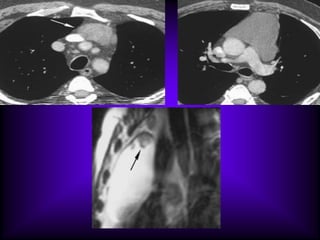

The CT features of benign

mediastinal cyst are

(a) a smooth, oval or tubular mass with a well-

defined thin wall that usually enhances after

intravascular administration of contrast

material,

(b) homogeneous attenuation, usually in the

range of water attenuation (0–20 HU),

(c) no enhancement of cyst contents, and

(d) no infiltration of adjacent mediastinal

structures.

Cysts that contain serous fluid typically have

long T1 and T2 relaxation values, which

produce low signal intensity on T1-weighted

MR images and high signal intensity on T2-

weighted images.

Because cysts containing nonserous

fluid can have high attenuation at CT,

they may be mistaken for solid

lesions. MR imaging can be useful in

showing the cystic nature of these

masses because these cysts continue

to have characteristically high signal

intensity when imaged with T2-

weighted sequences regardless of the

nature of the cyst contents